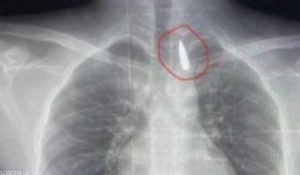

الطفل تعرض لطلق ناري في الرأس فاخترق جسده واستقر المقذوف داخل تجويف القفص الصدري قرب الشريان الأورطي، أكبر وأهم شرايين الجسم والمسؤول عن تغذية جميع الأعضاء الحيوية بالجسم.

جراحة معقدة.. إنقاذ حياة طفل من غزة مصاب بمقذوف في صدره .